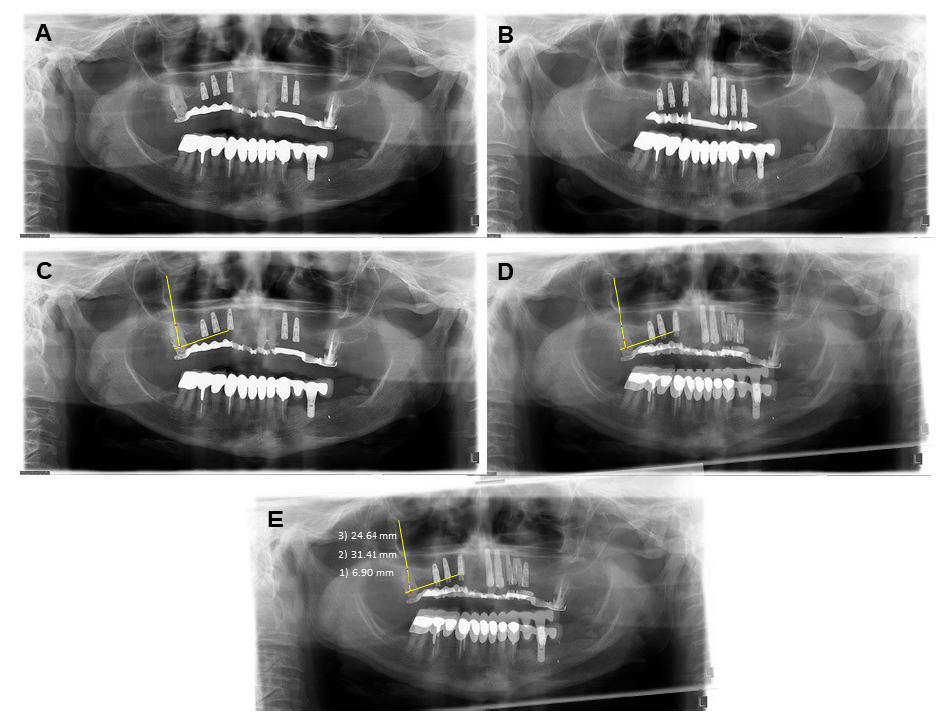

Matching and measurement technique: panoramic radiographs were used to measure sinus dimensions before extraction and at least 6 months after extraction. PowerPoint® software (Microsoft office 2016) was used to match the two radiographs using the following method [17]: the two images were set for transparency and then superimposed in the region of interest. Fixed reference structures, such as teeth and dental implants adjacent to the region of interest were selected for the matching procedure. Visual matching and alignment was performed by stretching or contracting the images until the reference structures were matched as accurately as possible. After matching, the radiographs were transferred into the Dimaxis Pro® measurement software (Planmeca Oy Helsinki Finland) version 4.1.6 for radiographic measurements (Fig. 2). The following measurements were performed:

Fig. 2.

Fig. 2.Measurement technique: (A) Baseline radiograph of tooth #17. (B) Final radiograph of tooth #17, 6 months following extraction. (C) Landmark identification and definition. (D) Superimposition of the two radiographs. (E) Measurements; the distance BC-floor (1), BC-roof (2), floor-roof (3).

1. Maxillary sinus sagittal circumference -- maxillary sinus wall circumference measured on the panoramic radiograph.

2. Distance between the bone crest (BC) in the middle of the extraction site and the sinus floor.

3. Distance between the BC in the middle of the extraction site and the sinus roof.

4. Distance between the sinus floor in the middle of the extraction site and the sinus roof.